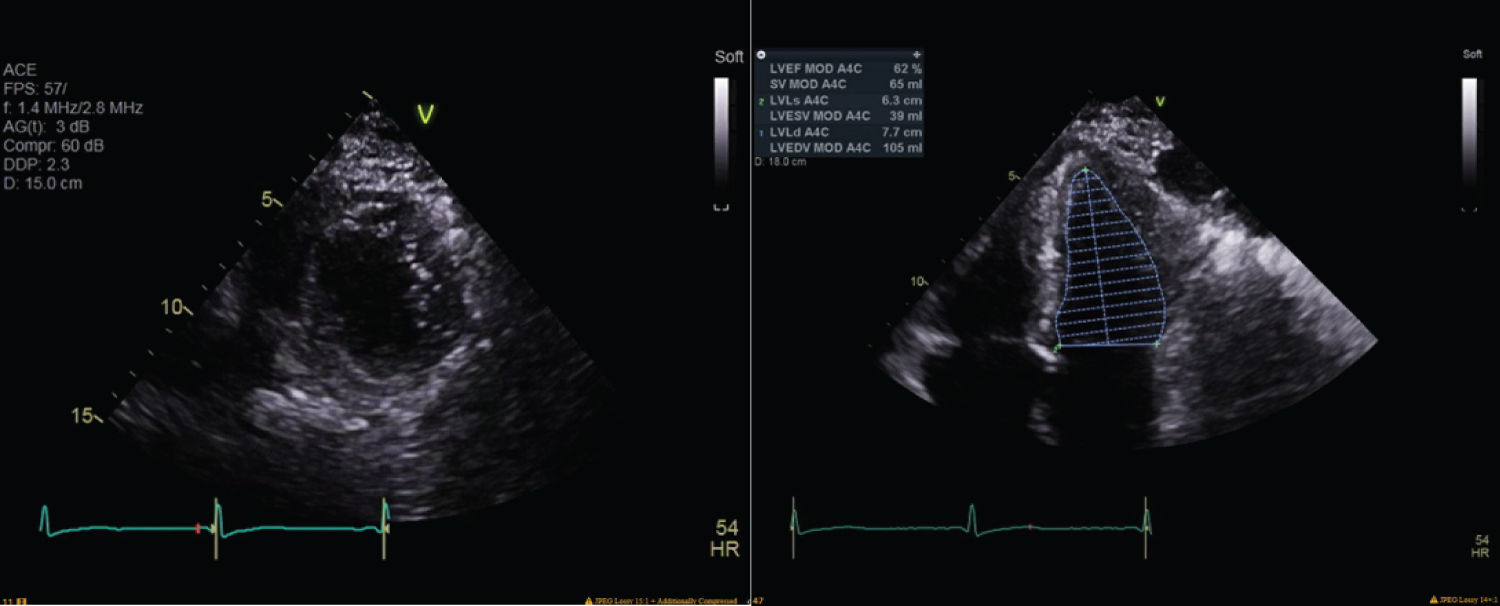

Transesophageal echocardiography was performed intraoperatively (Figure 1), six hours postop (Figure 2), and five days postop (Figure 3). EKG performed intraoperatively following ROSC demonstrated sinus rhythm with a borderline repolarization abnormality and a prolonged QT interval of 444 ms and QTc of 451 ms. Notably, there was no ST segment elevation present.

Figure 3: Echocardiography performed five days later revealed normal left ventricular size and mild hypertrophy, left ventricle ejection fraction of 64%, grade II left ventricular diastolic disfunction, moderate left atrial dilation, milt right atrial dilation, mild mitral regurgitation, moderate tricuspid valve regurgitation, mild aortic regurgitation, and an estimated right ventricular systolic pressure of 68 mmHg, consistent with moderately severe pulmonary hypertension. View Figure 3